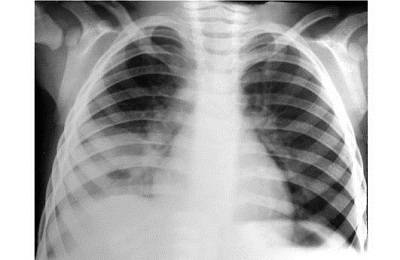

- Рентген грудной клетки показывает области консолидации и может дать полезные подсказки для определения возбудителя.

Рисунок 01: Внешний вид рентгеновского снимка грудной клетки при долевой пневмонии